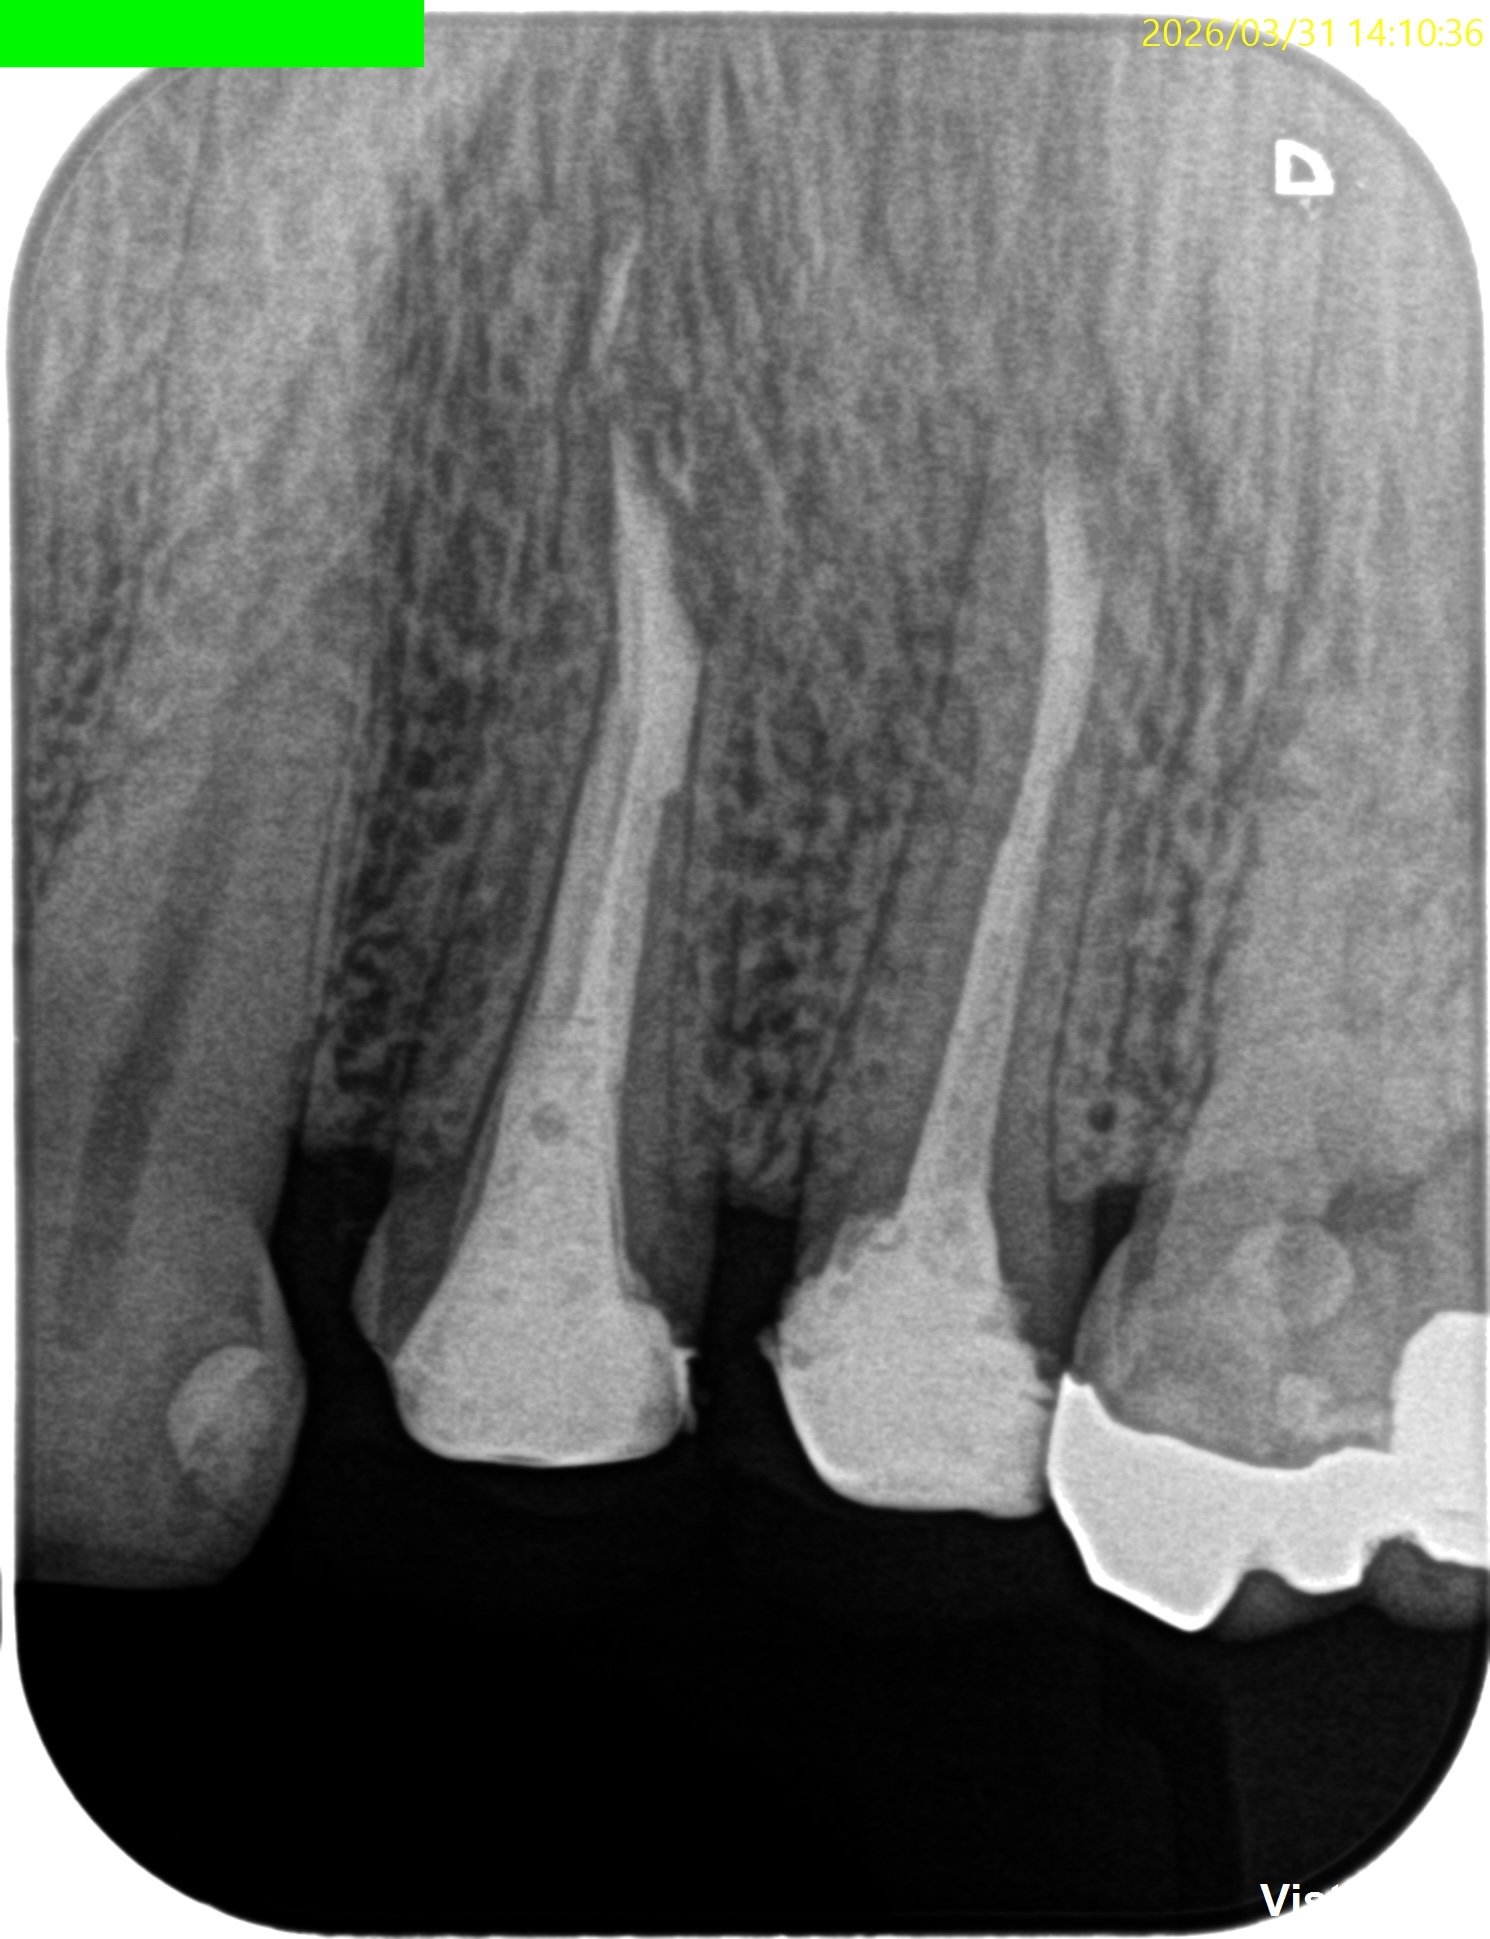

#12,13 Apicoectomy 6M recall(2026.3.31)

#12

術前・直後と比較した。

最終補綴はOKである。